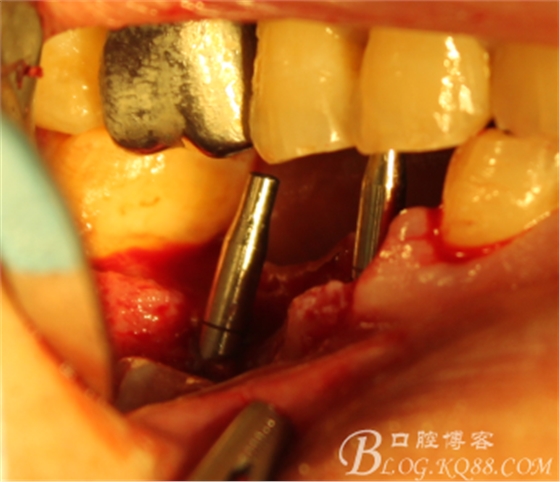

手術(shù)全程

翻瓣,拔除C5,跟尖端有吸收

徹底搔刮肉芽,定點,正對顎尖,擴孔同期行慢轉(zhuǎn)收集自體骨

植入植體

C6頰側(cè)填入自體骨,嚴(yán)密縫合關(guān)閉創(chuàng)口

三維檢查種植體位置,方向,平行度